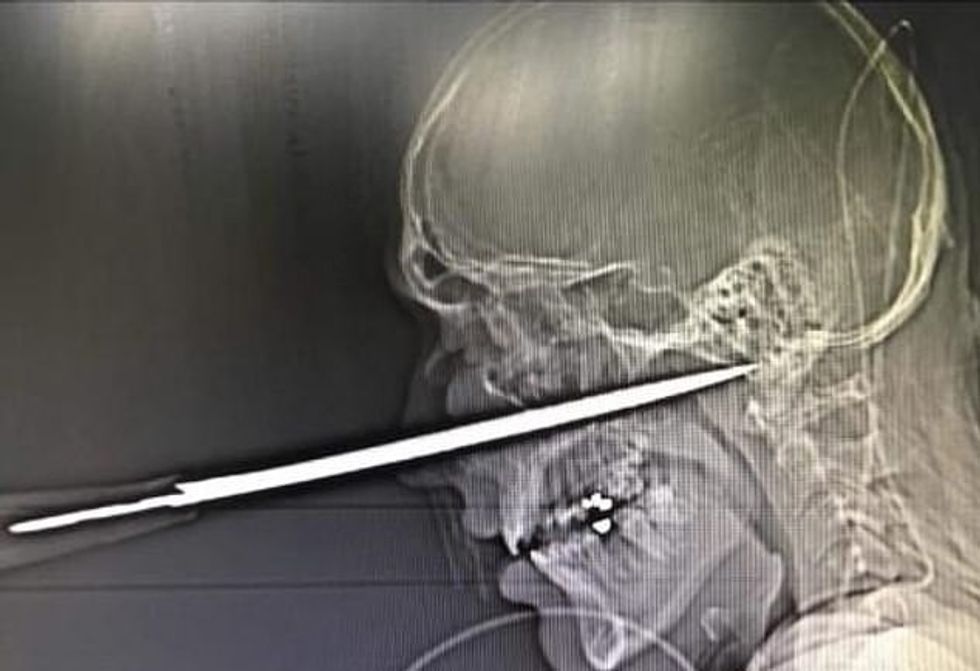

Në imazhet shqetësuese, shihet tehu i ngulitur në fytyrën e tij, menjëherë poshtë syrit të majtë.

Mjekët kanë konstatuar se sikur thika e gjatë 15 centimetra, të hynte vetëm një milimetër më thellë, do t’i dëmtonte arterien kryesore dhe do ishte fatale për jetën e tij.